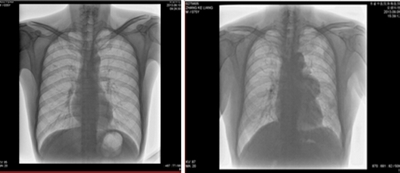

★適用于全身各部位攝影,包括常規(guī)攝影(立位攝影、臥位攝影等,如胸片、頸椎、腰椎、腹部、頭顱、四肢等)和特殊攝影(傾斜攝影、角度攝影等,如瓦氏位、骶髂關(guān)節(jié)、髕骨軸位、跟骨軸位等)。

★全身各部位透視(如胸透、腹透等)、透視下定位、透視下穿刺及透視下數(shù)字點片攝影。